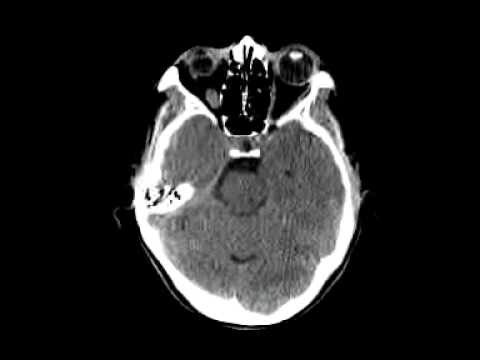

How Do I Know If My Cat Has A Brain Tumour - Cat Nap Benefits and Guide / For example, if you have a tumor near the part of.. How do i know when it is time to euthanize my cat? Scans provide a detailed 3d image of the brain by taking multiple pictures of the inside of your head. Find out more about eligibility for free nhs prescriptions and help with prescription costs. After taking a medical history, the doctor will examine the cat thoroughly. A normal temperature in cats ranges from 100.4º to 102.5º fahrenheit.

Brain ct scans may be done with or without contrast. contrast refers to a substance taken by. Treating your cat based on grading and staging when making a decision on how to treat your cat, it is very important to understand what grade and stage we are dealing with, because the treatment for each type is different. How do i know when it is time to euthanize my cat? Other signs of tumours (benign or cancerous) affecting internal organs can include loss of appetite, weight loss, lethargy and weakness, difficulty in breathing, limping and recurrent digestive problems. Brain tumors come in all shapes and sizes—and so do their symptoms.

My cat has been to the vet a few times recently, including to get her teeth cleaned, and this was never picked up/ felt, despite her having hyperthyroidism and feline asthma and being palpated at each vet visit. In order to diagnose brain tumors in cats, doctors take a detailed history from the cat's owner. Check your cat every now and then to see if he has developed any new masses on his body. Treatment includes surgery, radiation, chemotherapy or only focusing on the symptoms. Cancers reveal themselves in the form of growths and tumors. Scans provide a detailed 3d image of the brain by taking multiple pictures of the inside of your head. Secondary brain tumors, which are called metastases, are tumors that have spread to the brain from a tumor in another part of the body (i.e., metastasized). Primary brain tumors are tumors that originate from the tissues of the brain or the membranes covering the brain (meninges). I absolutely adore my cat and don't want her to suffer. The key to a tumor's symptoms really depends on its location, says theodore schwartz, md, a neurosurgeon with the weill cornell brain and spine center. A normal temperature in cats ranges from 100.4º to 102.5º fahrenheit. How do i know when it is time to euthanize my cat? Compare top pet insurance plans.